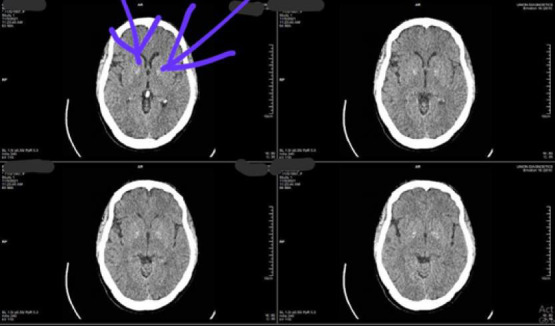

Case presentation: Here, we present a case of a middle-aged Nigerian woman with focal choreo-dystonia of the right upper limb accompanying the diagnosis of type 2 diabetes. Achieving euglycemia with insulin resulted in complete resolution of the choreo-dystonia.